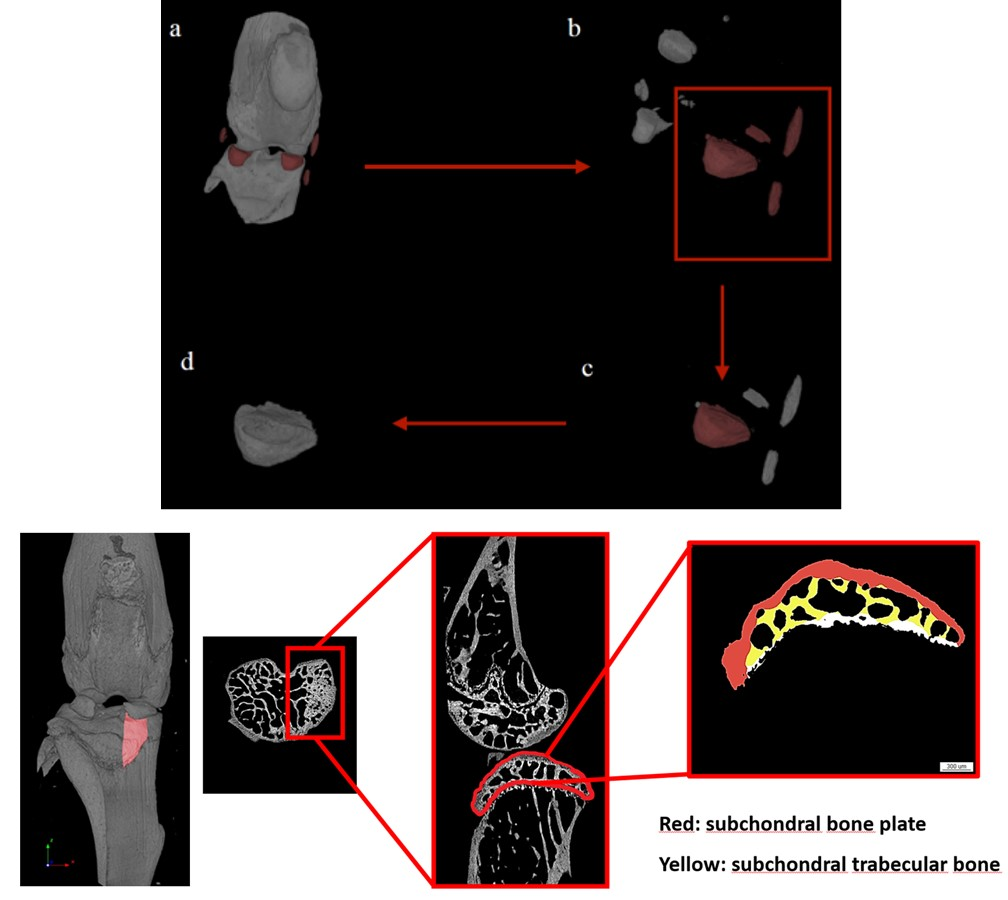

骨性关节炎小鼠模型(Ex vivo)-体积、结构性参数

小鼠交叉韧带横断术(ACLT)骨性关节炎。a. 骨性关节炎模型3D重建图,手术组软骨下骨大面积增生、磨损。b. 内侧半月板抓取示意图 c. 股骨软骨下骨松质骨横截面,手术组骨体积减少。d. 软骨下松骨结构性参数以及胫骨平面各项参数。

骨性关节炎模型造模手段通常有交叉韧带横断术(ACLT)和内侧半月板扰动(DMM)二者的评判标准和分析角度几乎一致,如胫、股骨软骨下松骨的结构性参数以及胫骨平面的厚度和孔隙度等,如果更关注软骨还可以进行离体组织造影来分析软骨。